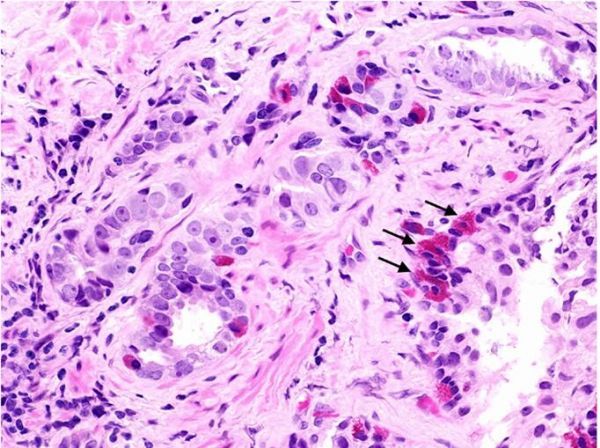

在这项研究中,研究人员发现miR-194能够促进前列腺癌转移。miR-194水平异常会刺激人类前列腺癌细胞系的迁移,侵袭和上皮间充质转化(EMT),稳定过表达miR-194还会增强肿瘤异种移植模型体内肿瘤的转移。与之相反,抑制miR-194活性可以抑制前列腺癌细胞系在体外和体内环境下的侵袭能力。前列腺组织中miR-194的水平还与疾病的侵袭性和不良结果存在相关性。